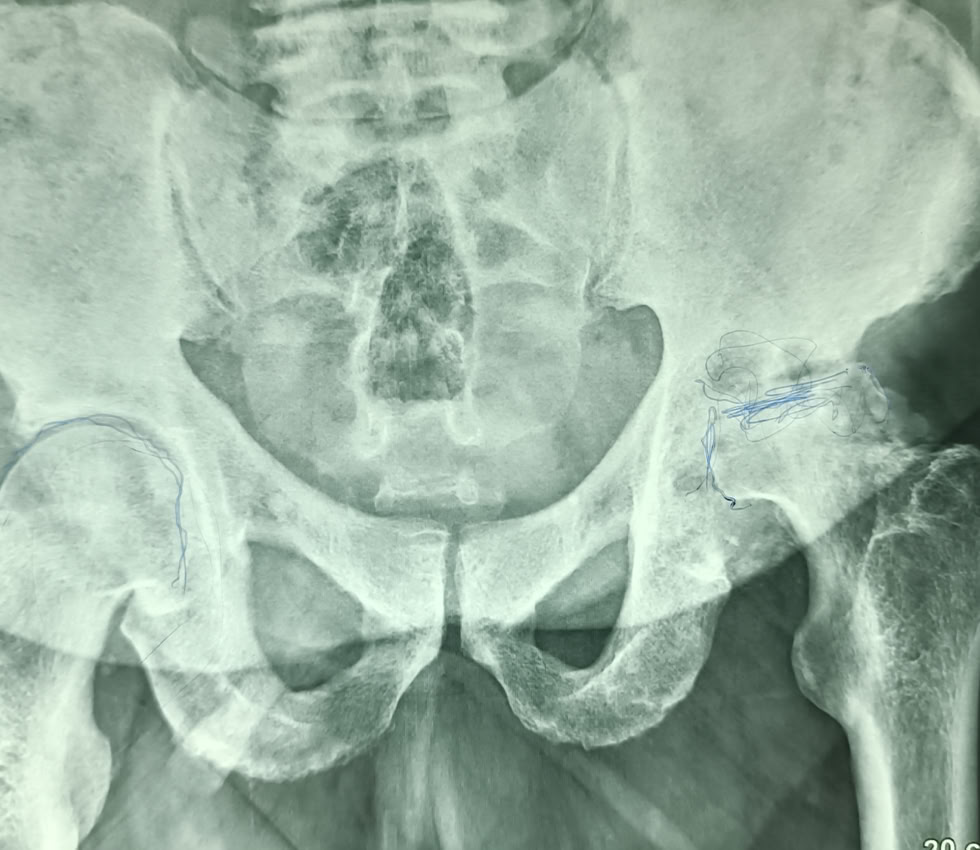

Gran carga de trabajo por las múltiples fracturas que hemos atendido, pero también hemos tenido tiempo de hacer una Prótesis Total de Cadera,  a un paciente de 71 años con una Necrosis Avascular de Cabeza Femoral . Le hemos mejorado la calidad de vida, ya que estaba prácticamente inválido y aquí podemos ver como se maneja caminando a las 48 h de la intervención